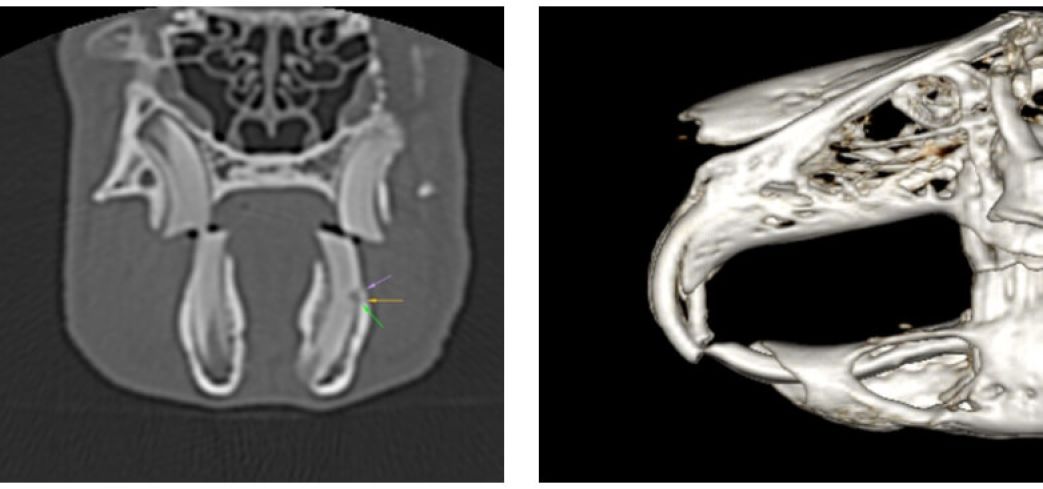

L’esame TAC rappresenta ormai il gold standard per la valutazione delle patologie del cavo orale di conigli e piccoli roditori (cavie, cincillà…). Per le caratteristiche particolari dei loro denti, infatti, conigli e piccoli roditori sono predisposti a problemi di malocclusione, allungamento dentale, ascessi e fratture. In tutte queste situazioni, la TAC garantisce la massima precisione diagnostica, più accurata di quanto si riesca ad ottenere dalle tradizionali radiografie. La possibilità di ricostruzione in 3D in corso di patologia dentale, inoltre, rappresenta un valido aiuto pre-operatorio per programmare un intervento dentale.